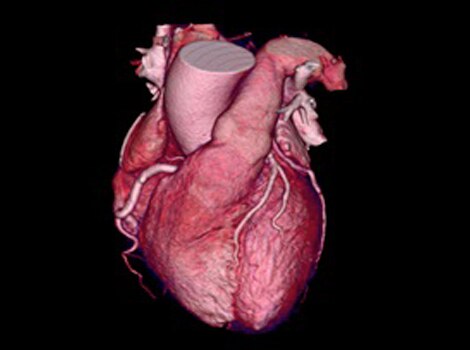

Revolution CT & CardioGraphe4

无论是否服用了 β 受体阻滞剂,可在任何心率下针对成像或综合心脏评估实现单次心跳、全心采集。5

了解更多信息

Revolution CT & CardioGraphe7

无论是否服用了 β 受体阻滞剂,可在任何心率下针对成像或综合心脏评估实现单次心跳、全心采集。8

Revolution CT & CardioGraphe3

无论是否服用了 β 受体阻滞剂,可在任何心率下针对成像或综合心脏评估实现单次心跳、全心采集。4 了解更多信息

无论是否服用了 β 受体阻滞剂,可在任何心率下针对成像或综合心脏评估实现单次心跳、全心采集。4